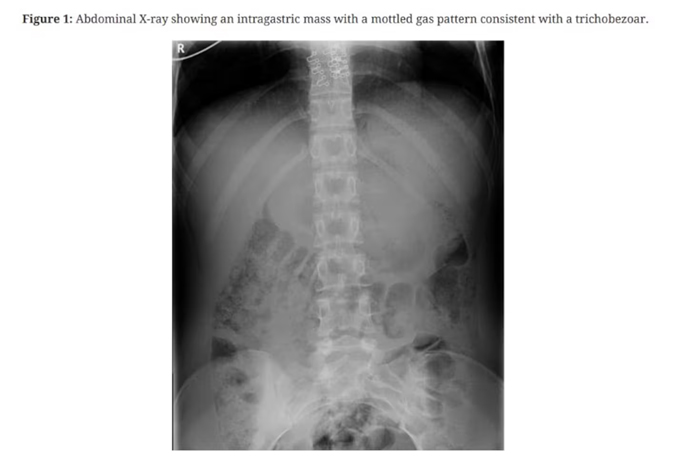

One was an abdominal X-ray showing “an intragastric mass with a mottled gas pattern, consistent with a trichobezoar”.

Doctors and staff connected to the case at Tauranga Hospital said the girl presented with pain and nausea, before an X-ray showed an abnormally swollen abdomen and signs of a bezoar – a tightly packed collection of undigested material that becomes stuck in the digestive tract – later identified to be a large hairball.